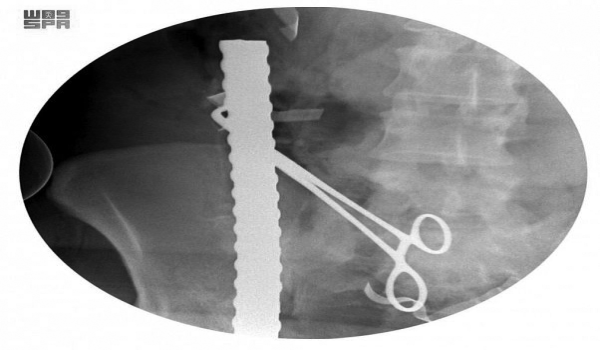

وبينت السبيعي أن السيخ الأول اخترق الجزء الأيمن من منطقة الفخذ بمحاذاة الشريان والوريد الفخذي الفرعي والأساسي مع منطقة البطن بمحاذاة الشرايين الحرقفية الكبرى وصولاً إلى شرايين الكلية اليمنى، واستقر بمحاذاة الاثنى عشر مما أدى إلى إصابة طفيفة في الاثنى عشر، مشيرةً إلى أن صور الأشعة أوضحت بأن السيخ الثاني اخترق منطقة البطن السفلى تحت السرة مما أدى إلى إصابة الأمعاء الدقيقة في أربع مناطق، واستقر في الجزء العلوي من المعدة بعد اختراق الجدار الخلفي والأمامي للمعدة، أما السيخ الثالث فقد تبين أنه اخترق الحوض من الجهة اليسرى مما أدى إلى كسر مضاعف في تلك الجهة من الحوض واستقر بمحاذاة العمود الفقري دون اختراقه ولله الحمد.

وأفادت أن مثل هذه الإصابات تستلزم إجراء جراحة من قِبَل فريق جراحي متمكن وبدقة عالية من المهارة؛ لما فيها من خطورة بالغة على حياة المصاب. وحول مراحل العملية أوضحت السبيعي أن السيخ الأول تم ‏استخراجه بعد السيطرة على الشرايين الكبرى، أما السيخين الآخرين فقد أُزِيلا بعناية شديدة كي لا يؤثّرا على الأعضاء المحيطة بالمنطقة المصابة مع ترميم الأعضاء المتأثرة جراء هذه الإصابة.